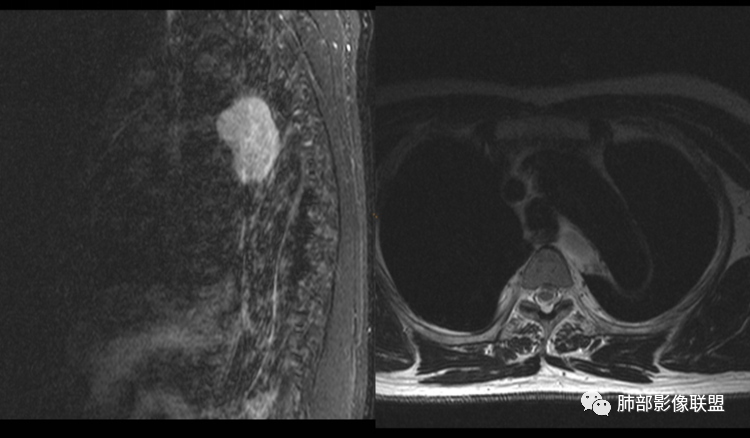

男性,43岁,体检发现后纵隔占位,边缘光整,CT示密度均匀,周围组织受压移位,无钙化囊变及脂肪组织,增强未见明显强化。MRI:T1示肿块信号较肌肉高,T2不均匀高信号。考虑为良性病变,第一是神经节细胞瘤,其次是支气管源性囊肿。

中年男性,无症状,后纵隔肿块,长径大矢状位于横径,质地偏软,塑形,等t1稍长t2,比较均质,增强轻微强化,与脊柱,主动脉,食管脂肪间隙存在,部分层面与脊柱相贴,骨质无改变,周围无肿大淋巴结,考虑神经源性肿瘤,节细胞神经瘤可能大,鉴别心包斜窦,淋巴瘤,淋巴管囊肿。

后纵隔占位,椭圆形,边缘不规则,CT低密度,MRI长稍长T1稍长T2信号,增强扫描未见强化,支气管受压。囊性病变,考虑支气管囊肿(常见,T1WI稍低“比水高”T2WI稍高,可能与其内含有粘液或蛋白有关);鉴别淋巴管囊肿(更软塑性性更大,接近纯水MRI信号长T1长T2,受周围挤压更明显,变形。);神经节细胞瘤瘤(增强可有轻度渐进性强化,也可不强化,关键是不常见),还有就是神经源性囊肿与肠源性性囊肿。

秦化君:

后纵隔占位;食道向右侧推移,病变质软,CT平扫密度均匀,边缘清晰光整,MRI 稍长T1,长T2高,脂肪抑制高信号。考虑纵隔良性囊性占位。先考虑支气管囊肿。其它类囊肿待除外。